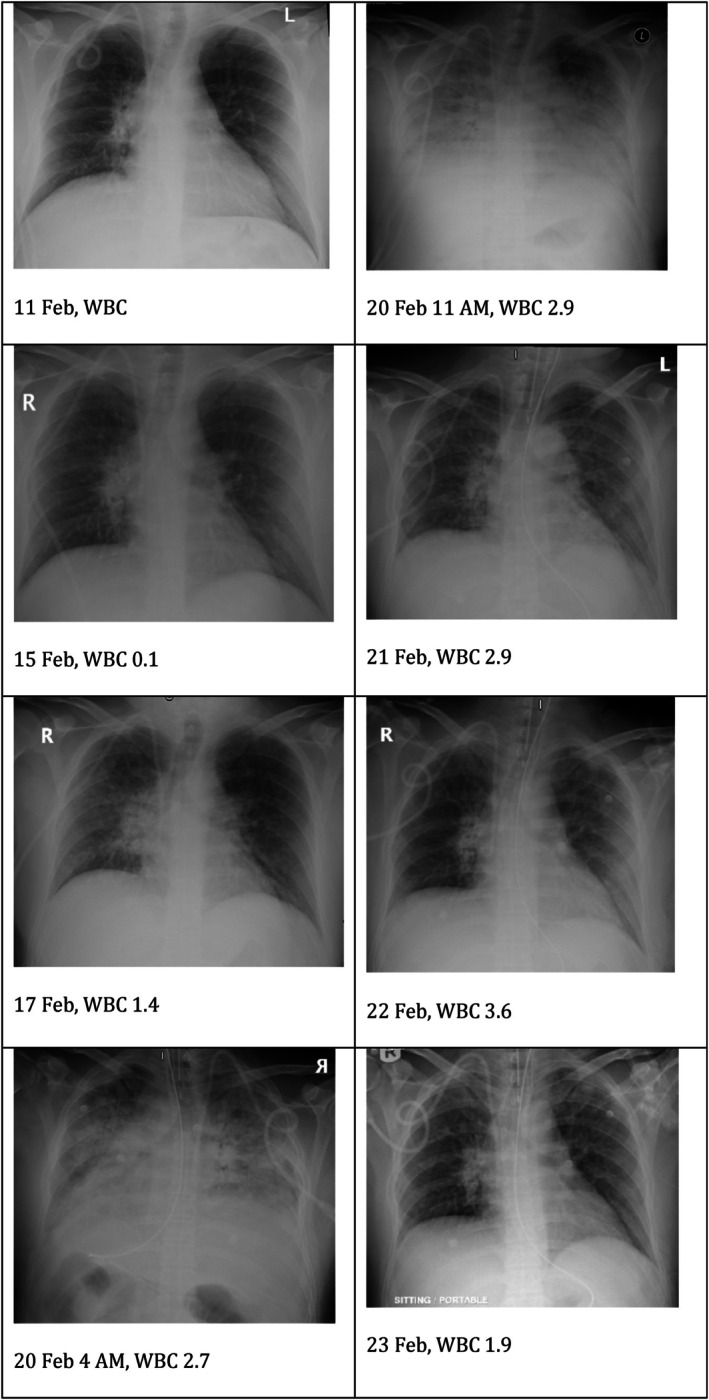

移植后综合征(PES)是自体造血干细胞移植(AHSCT)的一种重要且可能危及生命的并发症,表现为发热、皮疹和肺部受累。尽管具有临床意义,PES仍然是一个诊断挑战,经常被误认为是一种感染过程,导致适当治疗的延误。我们报告一例38岁男性复发霍奇金淋巴瘤和葡萄糖-6-磷酸脱氢酶(G6PD)缺乏症患者在AHSCT后发展为严重的PES。患者经历了严重的呼吸窘迫和精神状态的改变,需要插管和重症监护病房住院。尽管使用了广谱抗菌药物,他的病情仍在恶化,直到静脉注射皮质类固醇,随后出现了显著的临床反应。本病例强调了早期识别和适当管理PES的重要性。

Post-engraftment syndrome (PES) is a significant and potentially life-threatening complication of autologous haematopoietic stem cell transplantation (AHSCT) that presents with fever, skin rash and pulmonary involvement. Despite its clinical relevance, PES remains a diagnostic challenge and is often misidentified as an infectious process, leading to a delay in the appropriate treatment. We report the case of a 38-year-old man with relapsed Hodgkin's lymphoma and glucose-6-phosphate dehydrogenase (G6PD) deficiency who developed severe PES following AHSCT. The patient experienced severe respiratory distress and an altered mental status, necessitating intubation and intensive care unit admission. Despite broad-spectrum antimicrobial coverage, his condition deteriorated until intravenous corticosteroids were administered, with a subsequent remarkable clinical response. This case highlights the importance of the early recognition and appropriate management of PES.